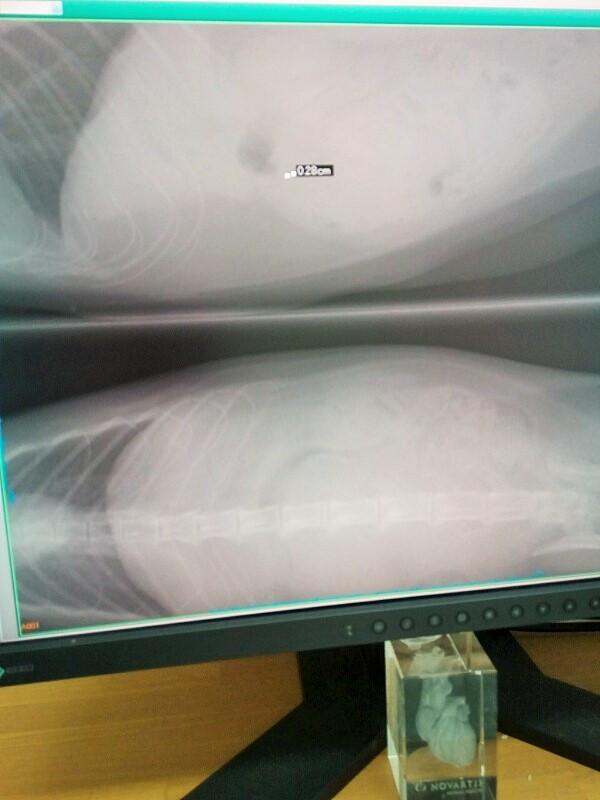

そこでまず触診…んーわかり辛い…との事でレントゲン

そこで発覚!!

硬く触った物は腎臓で別に異常なし(良かった)

ただ違う箇所に気になる影がある…朝食食べてすぐならそのせいかも?

何かが確実にある、腫瘍である可能性が高く場所的にリンパ腫の可能性が高い。